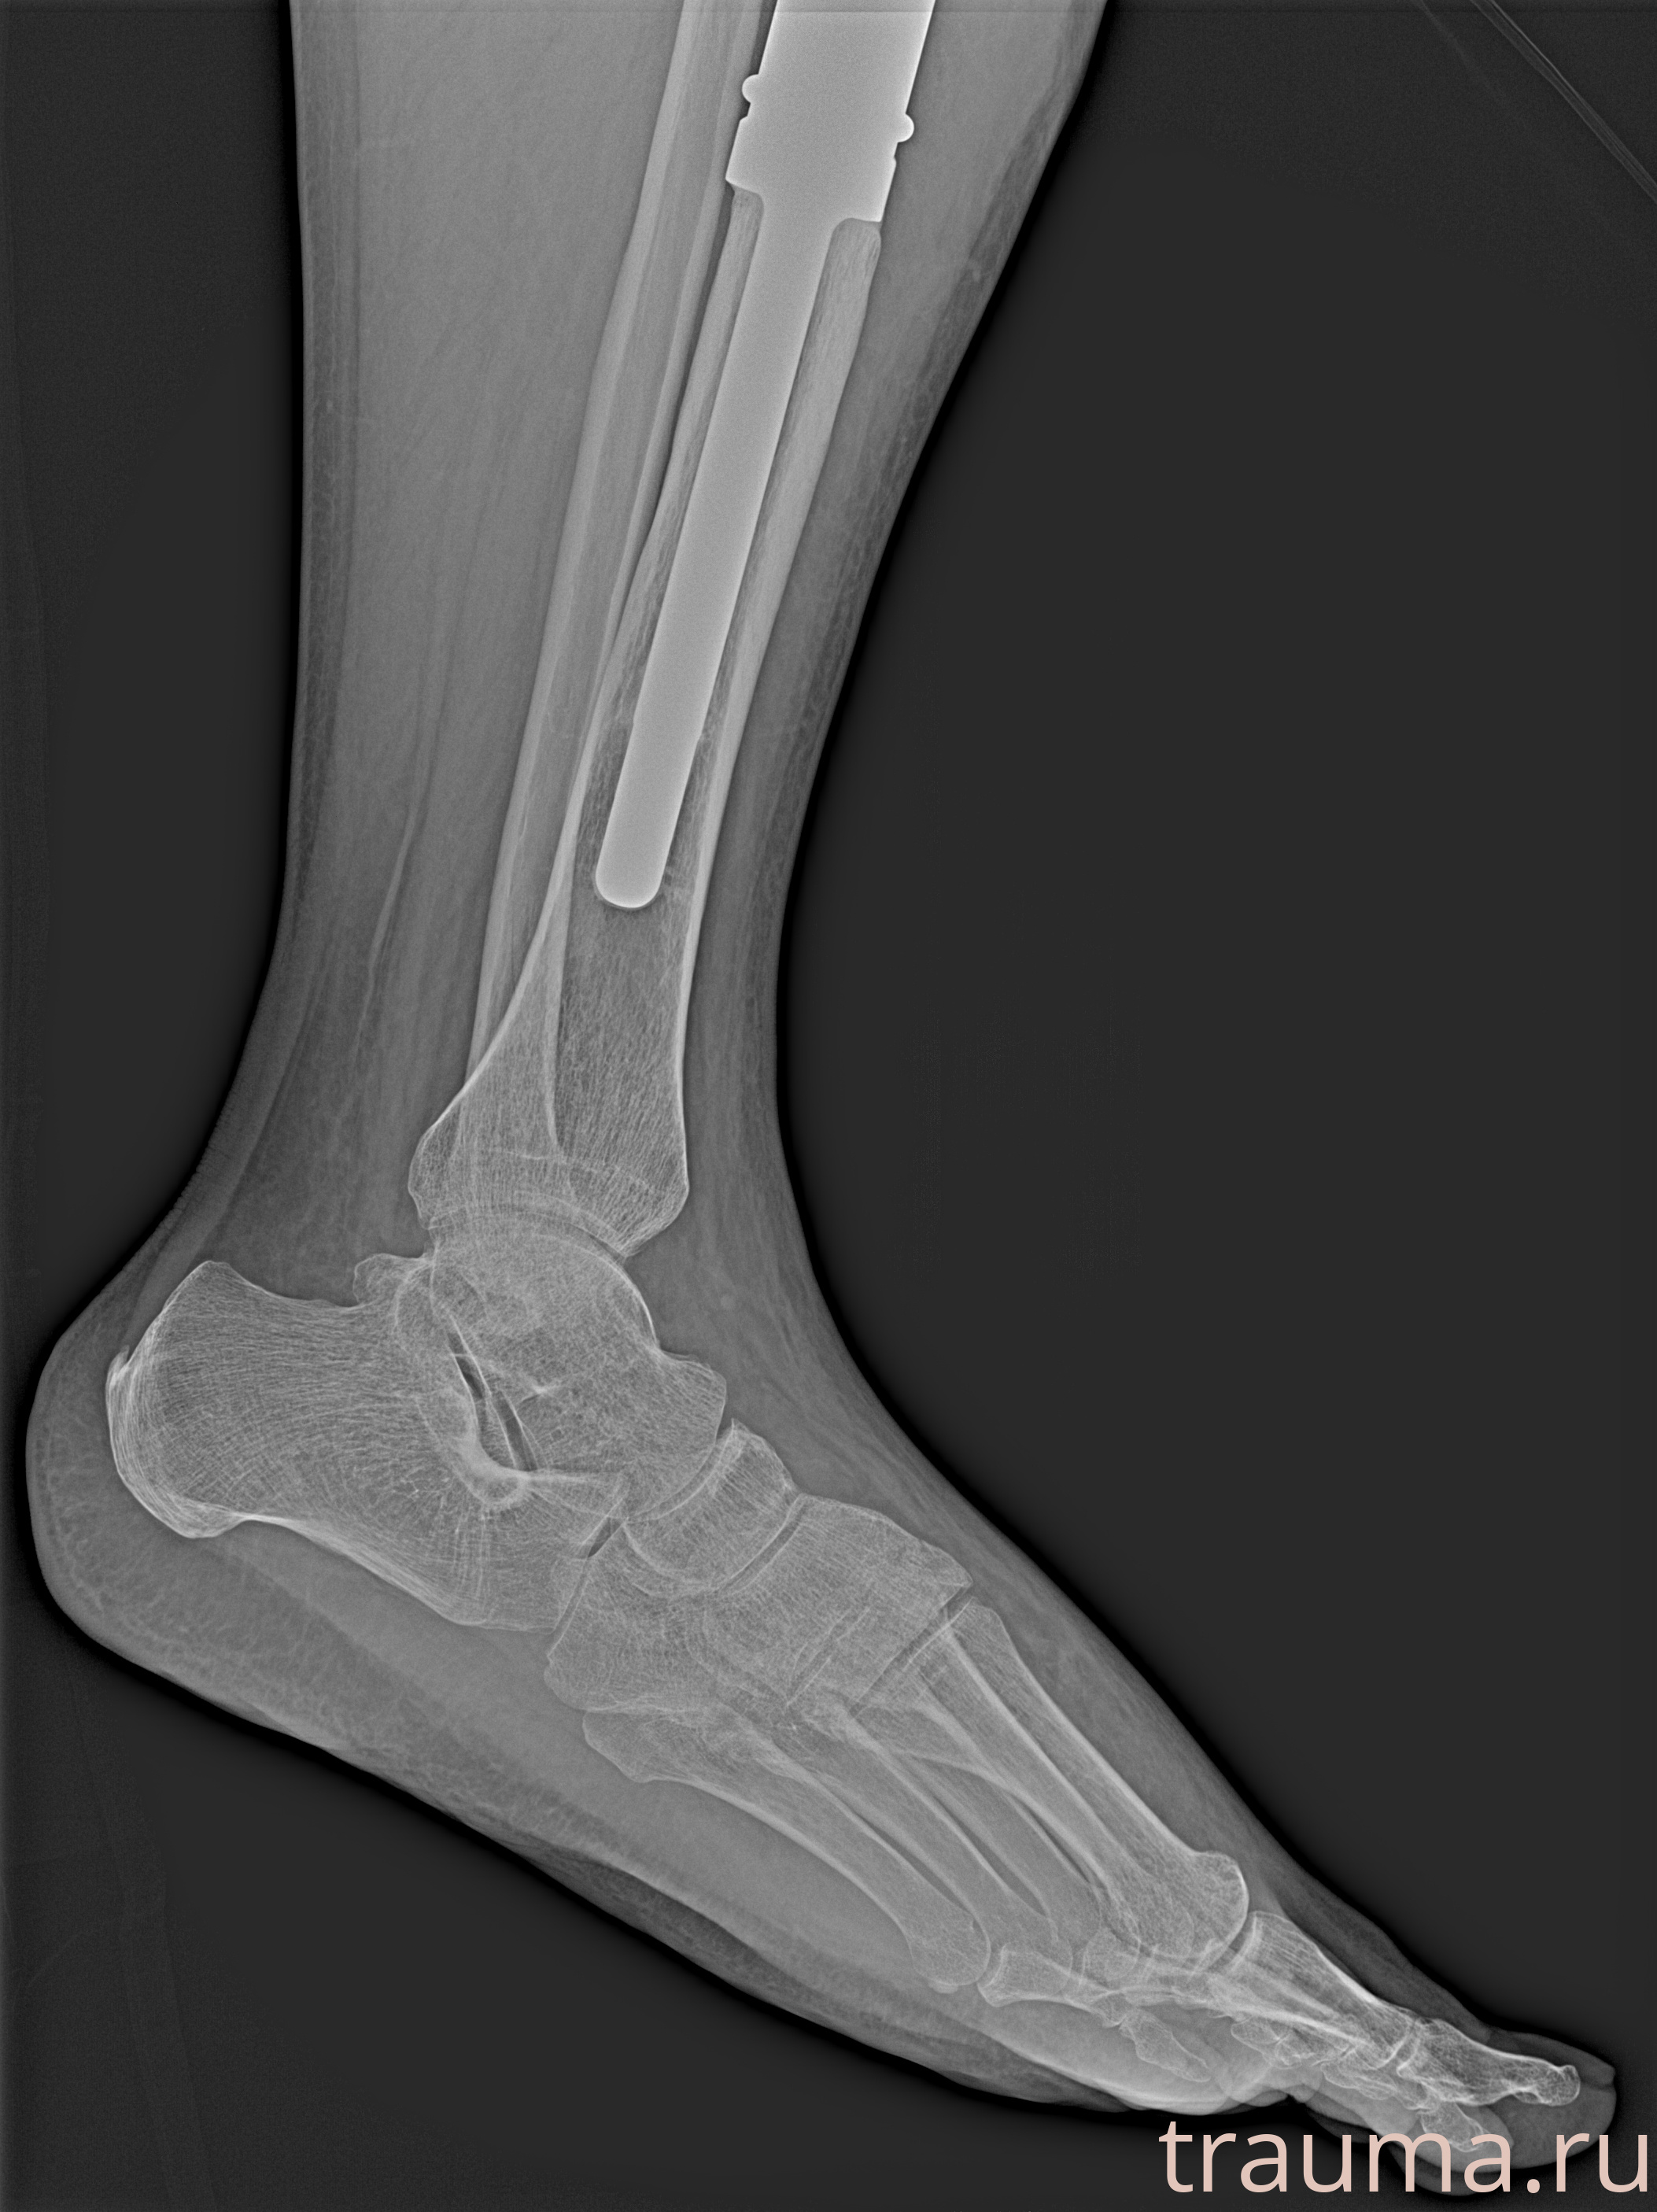

Рентгенограммы

Рентген на дому: по вашему адресу приезжает врач-рентгенолог, травматолог-ортопед с мобильным рентгеновским аппаратом, проводит диагностику травмы или заболевания, делает необходимые рентгенограммы, дает рекомендации по дальнейшему лечению. Получить качественные снимки в домашних условиях возможно благодаря уникальной методике, разработанной МосРентген Центром для института  Склифосовского